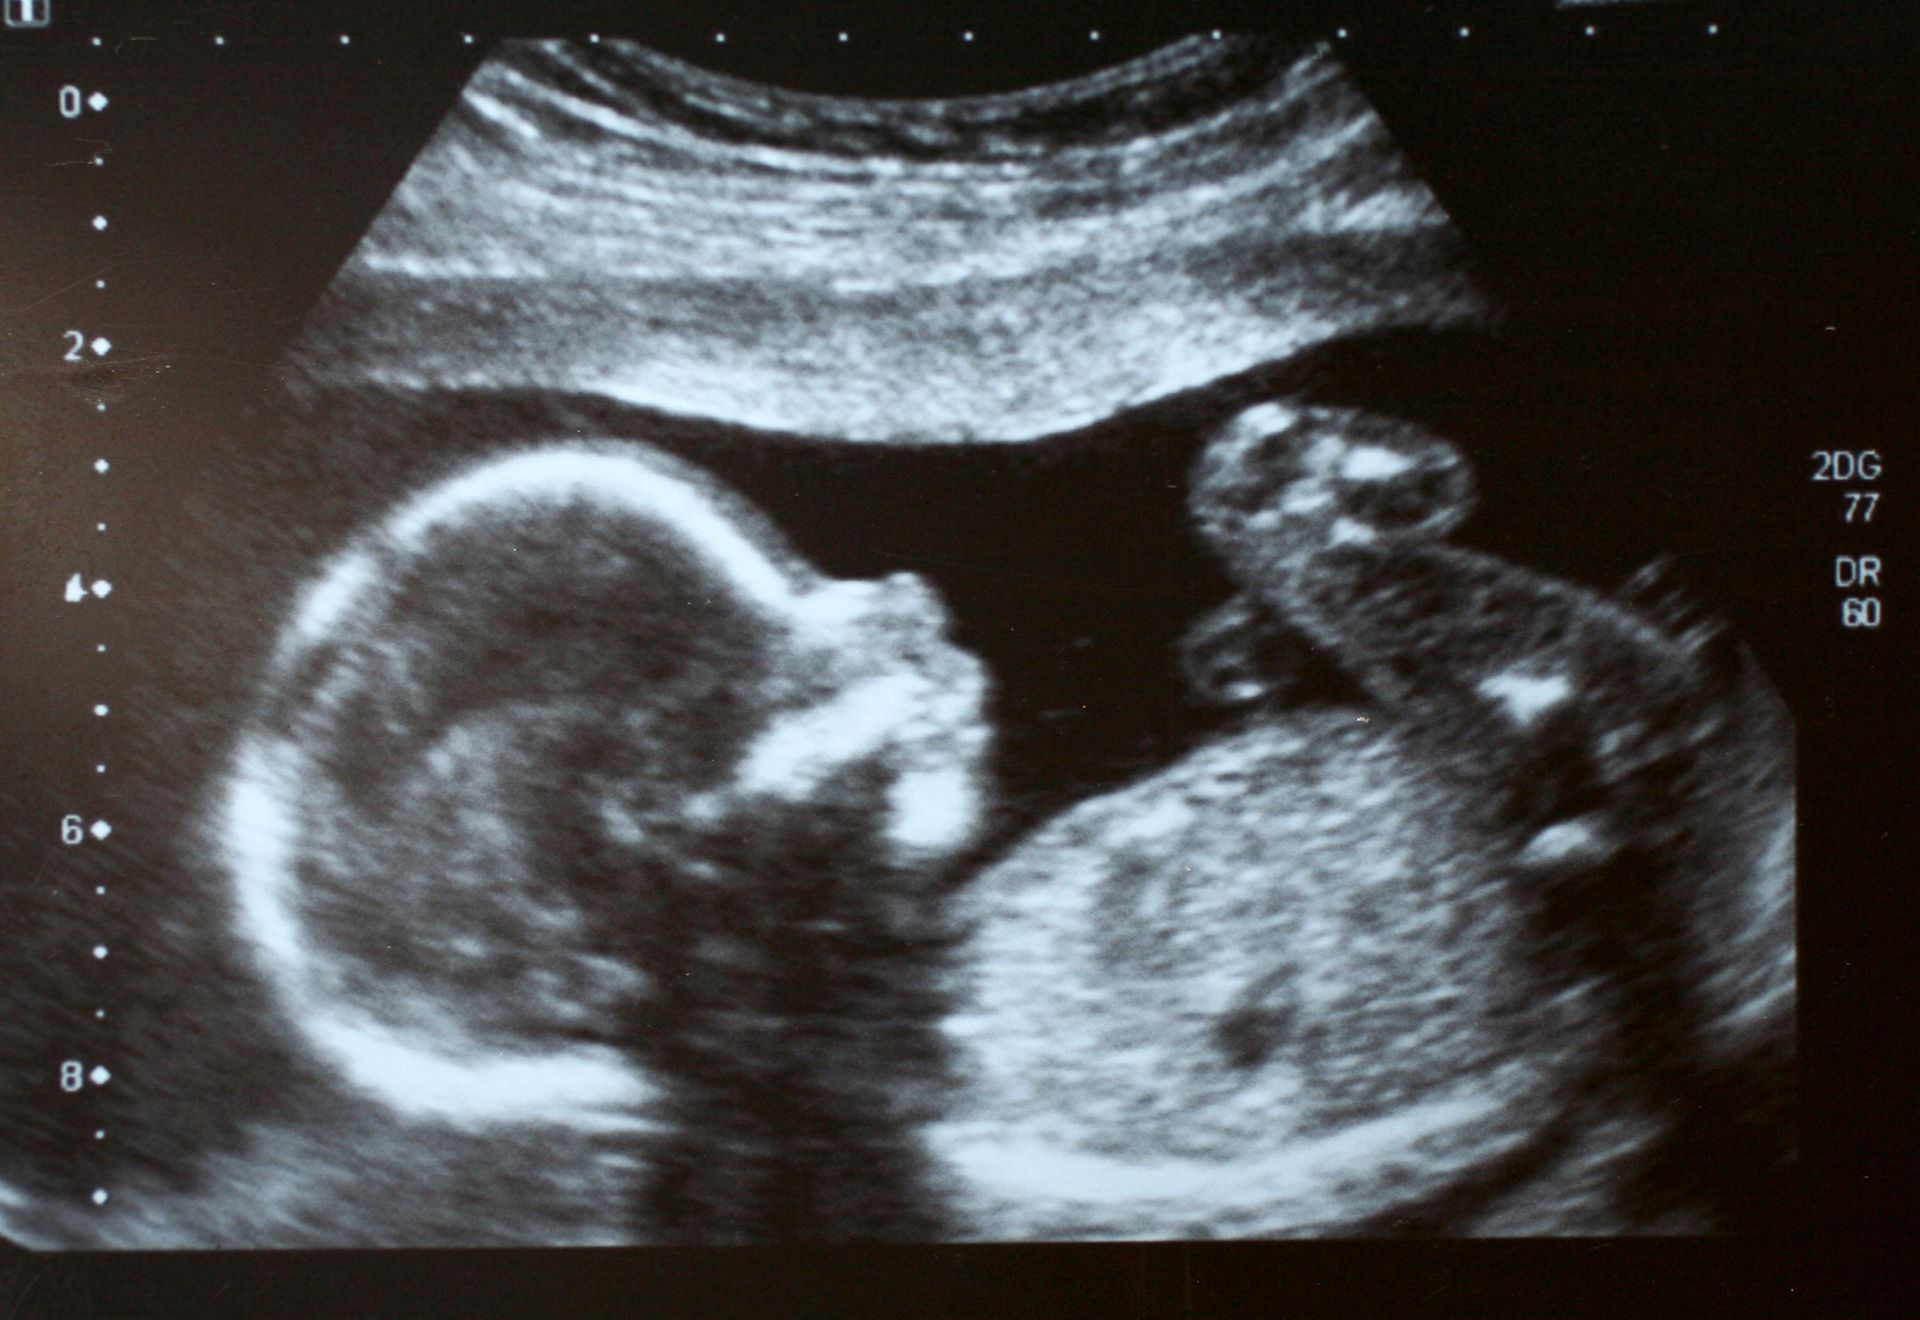

Diagnosi ecografica, ostetrica prenatale, ecografia ginecologica, chirurgia mini invasiva del basso tratto genitale femminile.